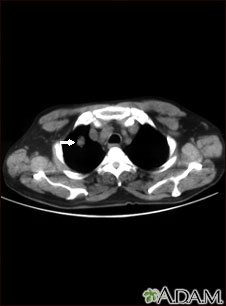

Your health care provider may suspect you have a fungal infection after x-rays of your lungs show the ball of fungus. Other tests that may be done include:

- Chest CT